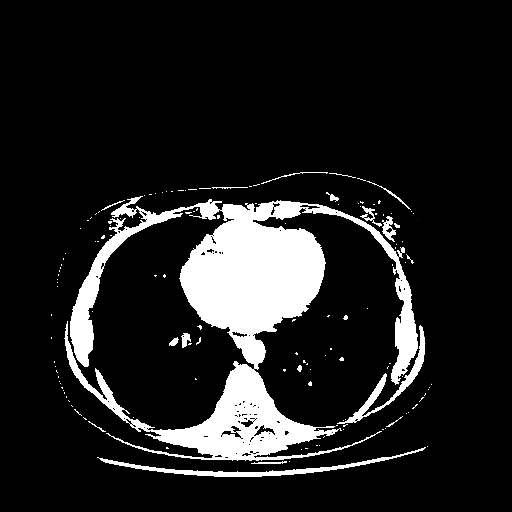

Slice 70 Targeting Evaluation

Slice: Slice_70

Conversion: NATIVE β†’ VENOUS

4Γ—3 grid: Rows show different image types (Original NATIVE, Reconstructed NATIVE, Original VENOUS, Generated VENOUS), Columns show windowing techniques (No Window, Lung Window, Mediastinum Window)

Generated VENOUS CT scan (A→B translation)

Full window (WL 1023.5, WW 4095 β†’ Low βˆ’1024, High +3071)

Actual HU range: [-1024.0, 3071.0]